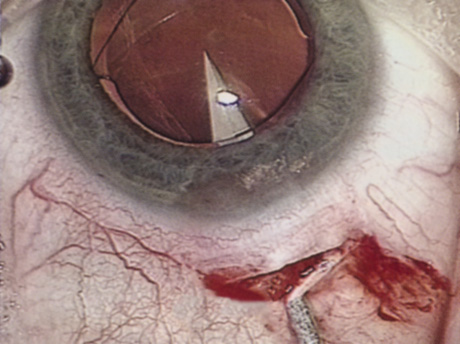

HYDRODISSECTION Hydrodissection can be performed after the surgeon has successfully completed capsulorrhexis.97 If the capsulorrhexis is not intact, fluid forced around the interior of the capsule may cause the bag to splay open. With capsulorrhexis, hydrodissection is a safe and extremely useful maneuver. Hydrodissection can be thought of as two maneuvers: hydrodelineation and cortical cleaving hydrodissection. By placing a 27-gauge cannula on a syringe filled with balanced saline solution (BSS), the surgeon can direct fluid beneath the residual anterior capsular rim to create a cleavage plane. Depending on the direction the fluid wave takes, different lamellae of the cataract will be separated. Hydrodelineation is the term used when the cleavage plane separates the adult nucleus from the fetal nucleus or the adult nucleus from the more peripheral epinucleus. Hydrodelineation often results in the characteristic golden ring sign (Fig. 11). Cortical cleavage occurs when the cortex is separated from the capsular bag (Fig. 12). Finding the cortical cleavage plane may be facilitated by gently lifting the capsular margin away from the cortex with the BSS cannula before injecting. Several small bursts of fluid allow the surgeon to monitor progress of the fluid wave. When dealing with a soft nucleus, the authors strive to perform true cortical cleaving hydrodissection. For a hard nucleus, hydrodelineation allows manipulation of less of the nuclear bulk, although the remaining epinuclear shell must be addressed in an additional step. Hydrodelineation is particularly useful if the nucleus is not freely mobile after cortical cleaving hydrodissection.